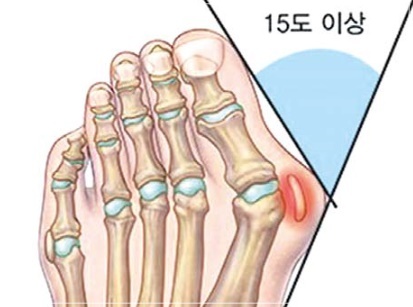

무지외반증은 엄지발가락이 둘째발가락 쪽으로 심하게 휘어져 엄지발가락 관절이 안쪽으로 돌출된 상태를 말하며, 심한 경우에는 엄지발가락이 둘째발가락과 엇갈리는 정도까지 돌아가기도 합니다. 특히 앞이 좁고 굽이 높은 신발을 자주 신는 여성에 흔한 대표적인 족부 질환입니다.

엄지 발가락의 튀어나온 관절부분(건막류)이 신발에 눌려 통증을 호소하는 것이 주 증상이나 엄지발가락이 둘째발가락 쪽으로 휘어져 있고, 관절이 안쪽으로 돌출되어 있습니다. 돌출된 관절은 서 있거나 걸을 때 자극을 받아 빨갛게 변하고 굳은살이 잡히며 염증과 통증이 발생합니다. 엄지발가락이 제 역할을 하지 못하니 발의 다른 부위에도 통증이 생기고 심해지면 발 모양의 변형, 허리의 통증 등이 발생합니다.

무지외반증 여부의 진단은 시진과 촉진(발가락 모양, 굳은살 등)으로 가능하지만 치료 방침을 결정하기 위해서는 방사선 검사가 필요합니다. 뼈와 뼈가 이루는 각도, 관절의 변형과 염증, 운동 범위 등을 측정합니다.